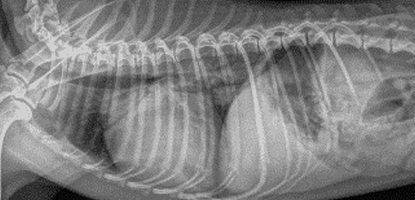

A Pós-graduação Lato Sensu em Radiologia Veterinária foi desenvolvida para médicos-veterinários que desejam aprimorar sua capacidade de interpretação dos exames de imagem e utilizá-los de forma criteriosa na tomada de decisão clínica e hospitalar. O curso tem como foco a radiologia veterinária aplicada à prática clínica, capacitando o aluno a reconhecer padrões radiográficos, compreender as limitações do método e correlacionar os achados de imagem com o histórico, o exame físico e a condução adequada dos casos.

Ao longo da formação, o aluno desenvolve um raciocínio diagnóstico estruturado, aprendendo não apenas a identificar alterações, mas a entender quando a imagem é decisiva, quando é complementar e quando outros métodos diagnósticos devem ser indicados, sempre com responsabilidade técnica e ética profissional.

A proposta do curso é unir a base teórica essencial à discussão prática orientada por casos reais, preparando o médico-veterinário para lidar com as situações mais frequentes da rotina clínica, bem como com cenários desafiadores que exigem interpretação cuidadosa e comunicação clara dos achados radiológicos.

O curso é estruturado para conectar a interpretação radiográfica à prática clínica, auxiliando o aluno a compreender como os achados de imagem influenciam diretamente a condução dos casos. As aulas priorizam a correlação entre imagem, sinais clínicos e histórico do paciente, promovendo um raciocínio diagnóstico objetivo, seguro e aplicável à rotina veterinária.

| Radiologia da região cervical e tórax de pequenos animais | 50 horas |

| Radiologia do abdômen de pequenos animais | 50 horas |